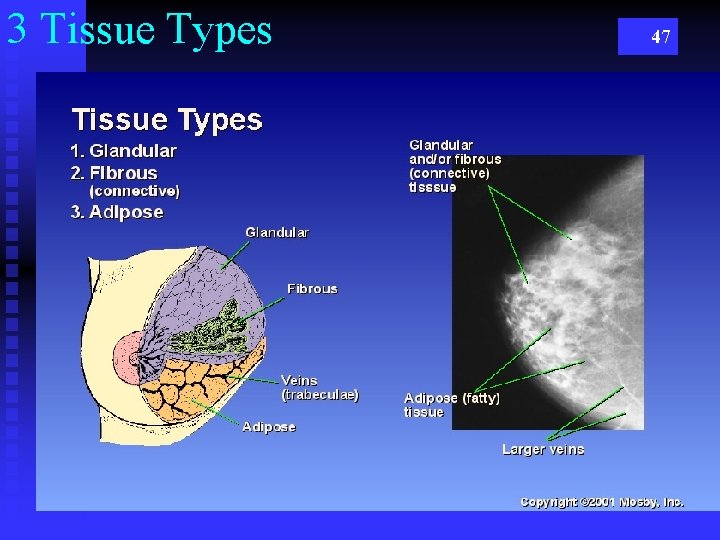

3 Tissue Types 47